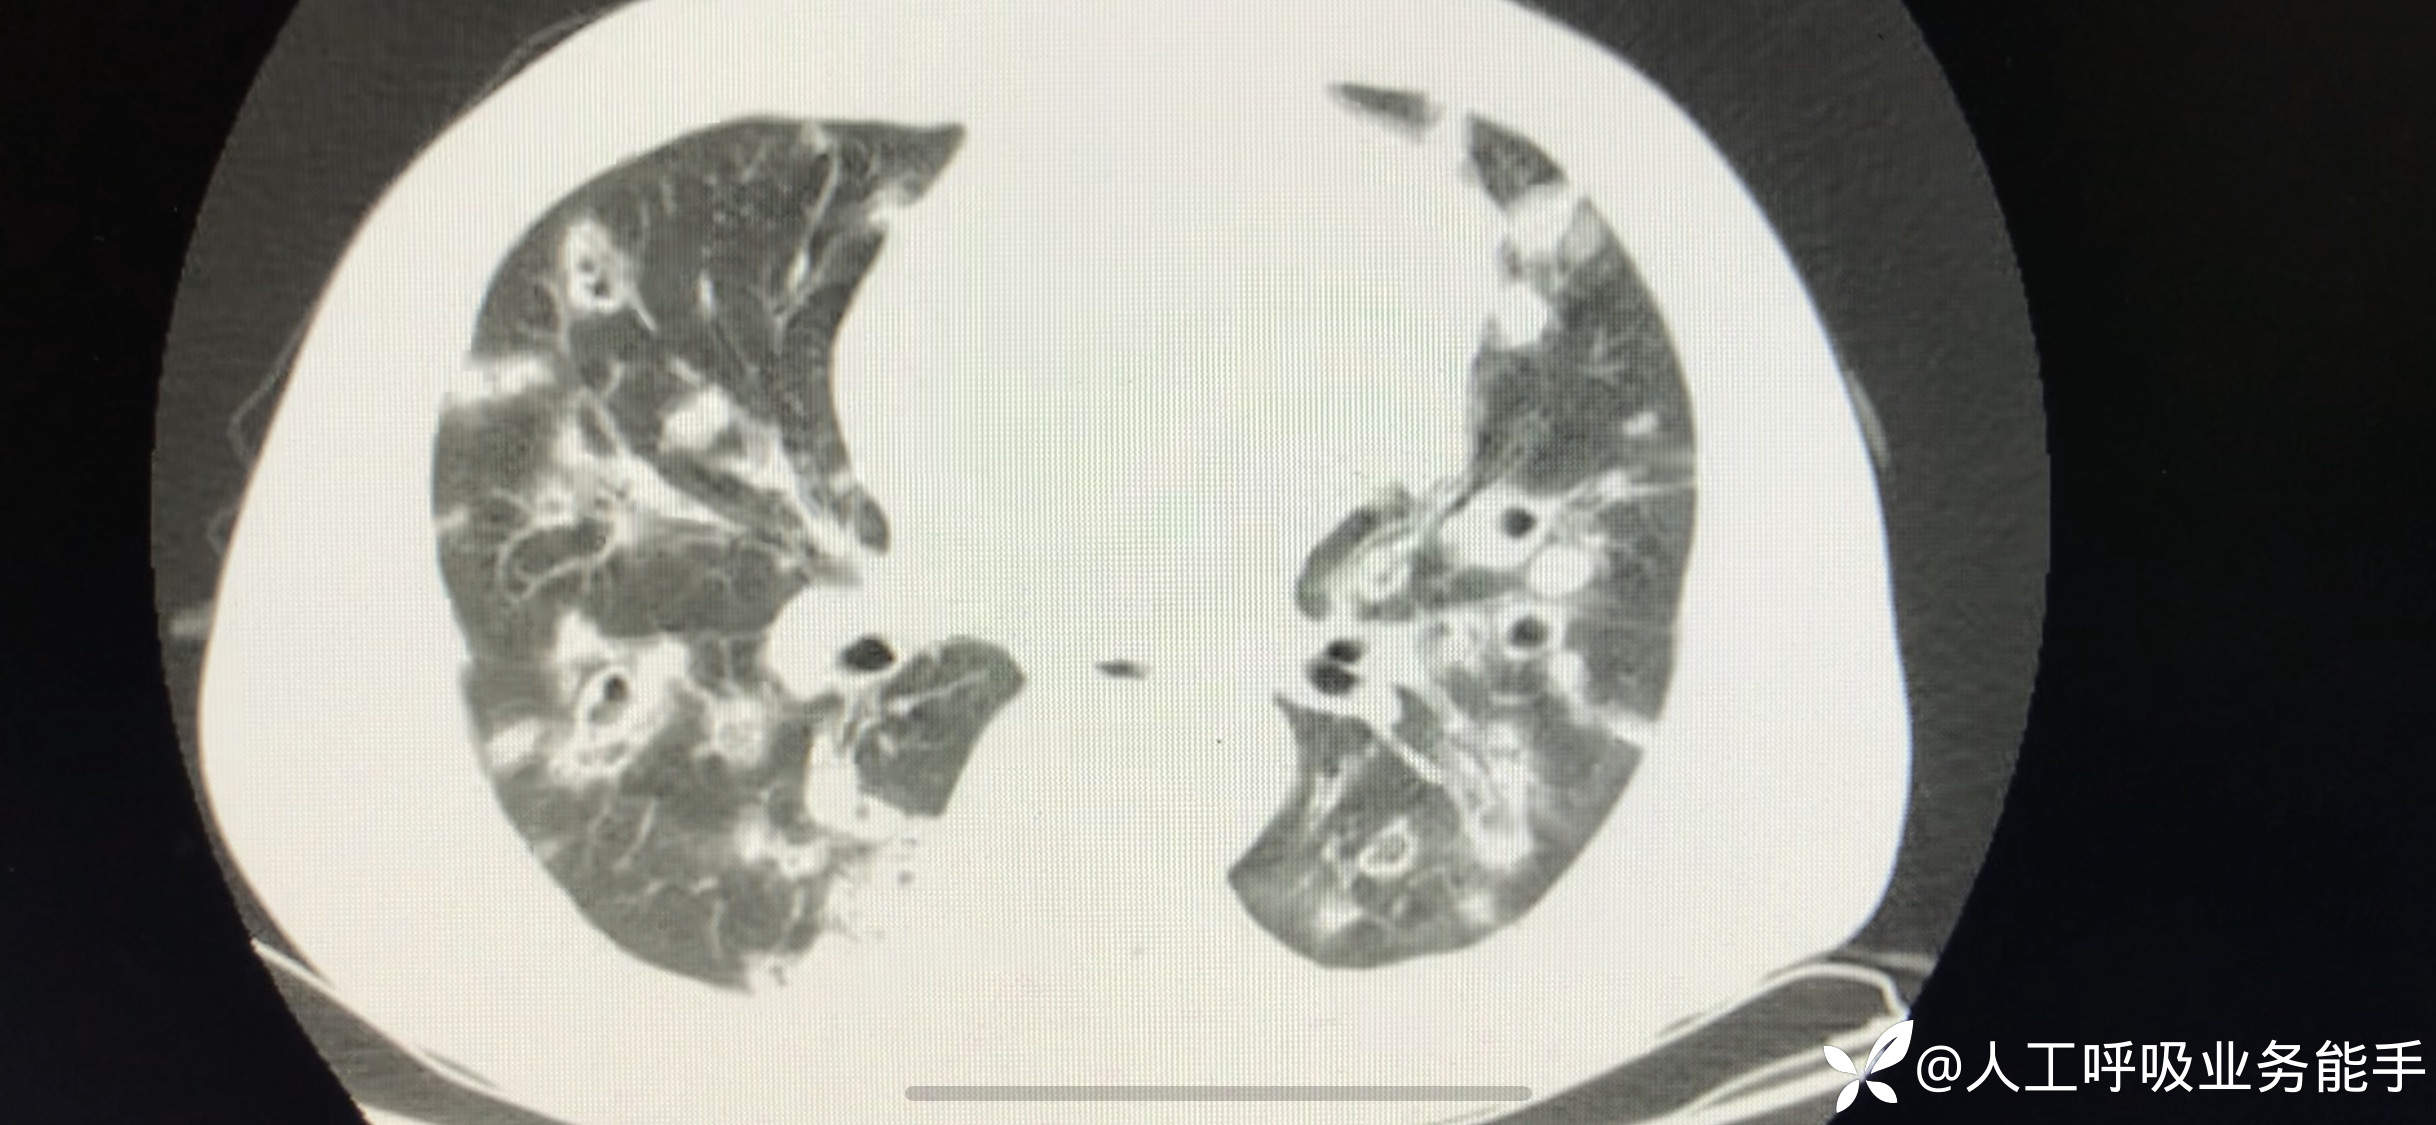

初诊影像: